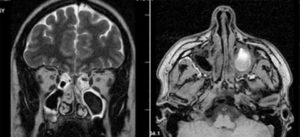

Рентгенологическая плотность мицетомы сравнима с плотностью металла. На снимке грибное тело отмечается как яркое пятно, которое окружают массы, менее плотные рентгенологически. Реже грибковый шар определяют при помощи МРТ.

Особенности МРТ-исследования в диагностике мицетомы